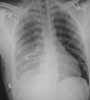

You order frontal and lateral uprightradiographs of the chest. Whatabnormalities are evident on thesefilms, and how will you proceed todetermine their cause?

Thefrontal (

A

) and lateral (

B

) radiographsreveal ill-defined opacities inthe middle and upper lobes of theright lung (

A and B, white arrows

)and thickening in the right apex (

A,yellow arrow

).You order a CT scan of thechest. An axial image at the level ofthe middle third of the left ventricleshows an opacity in the superior segmentof the right lower lobe (